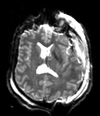

Slicer Registration Library Case 38: TBI

| T1pre | FLAIR | T1post | coronal T2 | SWI | EP50 | EP75 | EP100 |